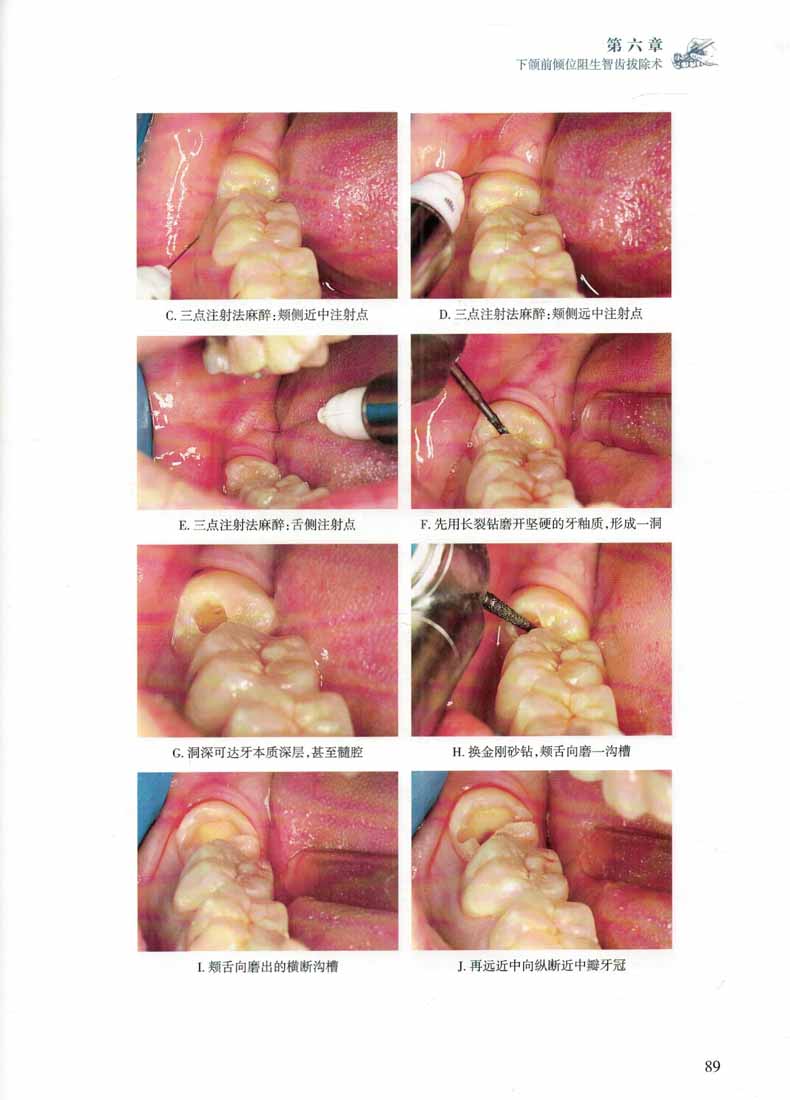

本書是筆者多年來應用渦輪鑽法拔除阻生智齒的臨床資料的總結,以病例圖片為主,配以文字和示意圖說明。

全書共分13個章,以圖解形式介紹了臨床上常用的阻生智齒分類方法,闡述了其應遵循的基本原則,並敘述了複雜阻生智齒鑽拔法臨床操作步驟、術中可能遇到的難點的處理方法以及術中、術後並發症的預防和處理。第13章還特別介紹了自體智齒移植術。本版在上版基礎上增加23例不同類型阻生智齒拔除術視頻,以更加生動的形式展現渦輪鑽法拔除阻生智齒。本書獻給熱愛牙槽外科、對阻生智齒拔除術感興趣的您。

本書一改傳統翻瓣鑿骨法拔除阻生智齒的手術思路,基於作者數十年拔除智齒的臨床經驗提出了渦輪鑽法拔除阻生智齒的手術思路,即:以潛鑽法先分牙、多分牙,以三角切齦代替翻瓣或小翻瓣,少去骨、不去骨或不首先去骨的地拔除阻生智齒。較之傳統方法,不僅降低了術者的操作難度,也在很大程度上減少了患者拔牙後的創傷及並發症。對相關臨床工作者有很大的實際指導意義。書中詳細闡述了應用該法拔除各類阻生智齒的具體步驟。本版不僅延續上版特色附大量精美圖片,圖文並茂,且在上版基礎上新增23個高清拔牙手術視頻,紙數融合,讀者可通過掃描二維碼形式輕鬆觀看。力求為廣大口腔醫師提供一冊專業 、內容實用、易讀易學的參考書。